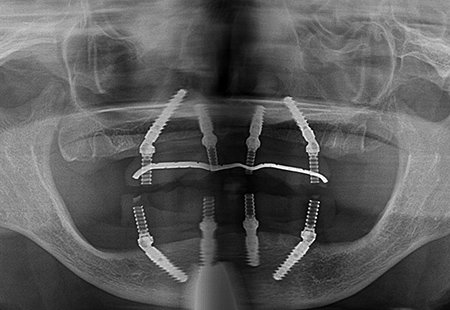

• 上顎インプラント3本とザイゴマ2本、下顎インプラント4本による上下オールオン4

術前

術後

年齢・性別 65歳・女性

治療期間 オペから上部セットまで6ヶ月、通院回数19回

治療費用 5,758,180円(税込)

治療内容 前歯のブリッジが取れ来院。下顎臼歯のデンチャーも使っていない状態。歯周病も重度で上下顎でしっかり噛みたいとインプラントを希望。